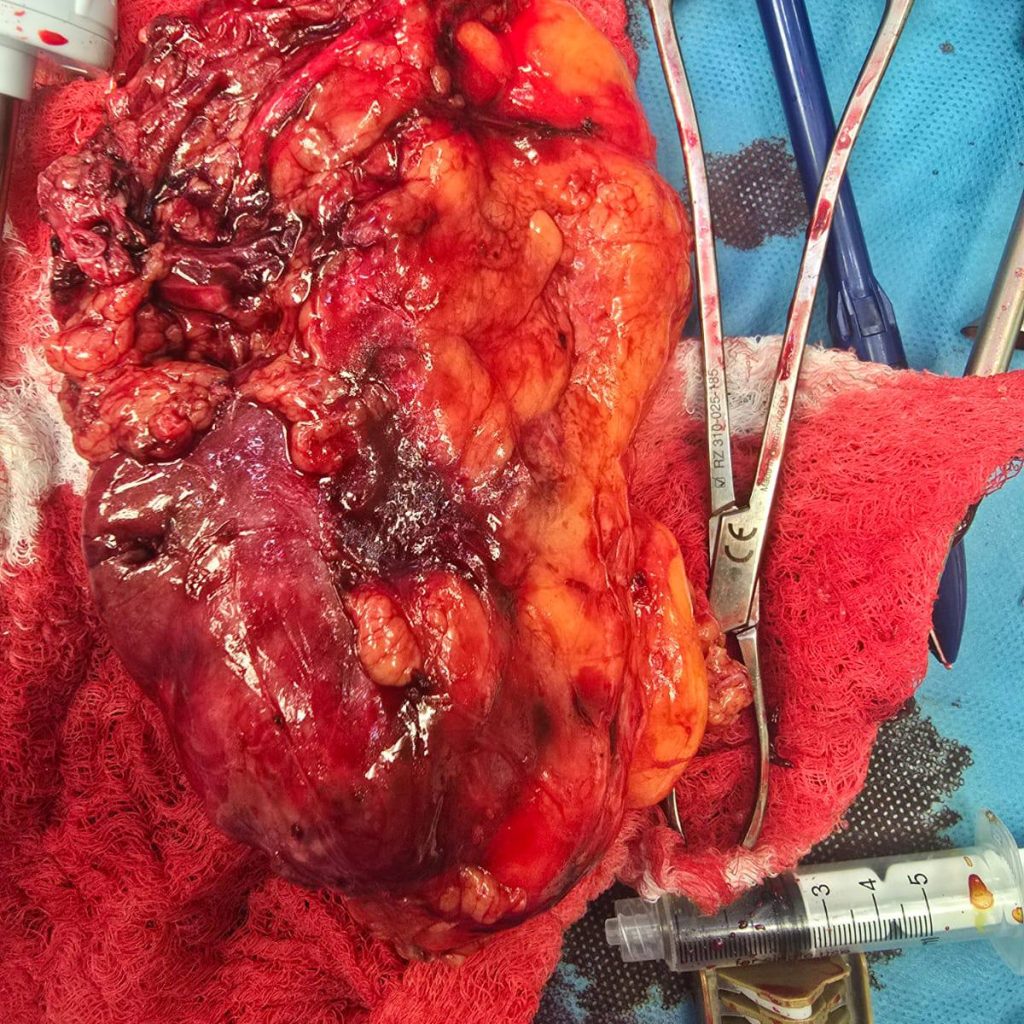

تمت تهيئة المريضة وفق بروتوكول تحضيري دقيق، بإشراف فريق متعدد التخصصات شمل جراحي المسالك البولية وأطباء التخدير، مع مراعاة حالتها المرضية المزمنة (السكري) لتقليل المخاطر المحيطة بالعملية.

وقد أُجريت الجراحة باستخدام تجهيزات طبية حديثة، واستغرقت قرابة ثلاث ساعات، تكللت خلالها بإزالة الورم بالكامل دون مضاعفات تُذكر.

أعقب العملية استقرار في العلامات الحيوية للمريضة، حيث نُقلت إلى مرحلة الإفاقة وهي بحالة عامة جيدة، وتخضع حاليًا لمتابعة طبية دقيقة ضمن خطة رعاية ما بعد الجراحة.